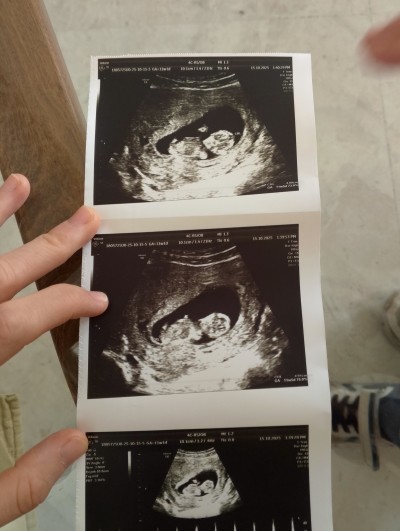

Kızlar cinsiyet tahmini yapar

image mısınız rica etsem ☺️☺️❤️

Gebelik haftası 12

Kesemiz aynı ve benim erkek

Keseden değilde 2. Resimde çıkıntı var sanki :) hakkınızda hayırlısı

Kese yuvarlaksa kız kese şekilli şukuluysa erkek derler seninki biraz şekilli duruyor canım

Erkeğe benziyor maşallah bu sene erkek senesi gibi. :D

Êrkêğê bênziyor canım

Nub çıkıntısı kıza benziyor ama net değil foto öğrenince yazın merak ettim simdi

Cinsiyetini öğrendim bugün kız dedi doktorumuz özelde öğrendik çok net❤️

Canım bence direkt kız. İlk fotoda bacaklarını açmış 😂 pipi gözükmüyor

Öğrendik bugün kız dedi doktorumuz özelde öğrendik doğrudur diye tahmin ediyorum kesin ve net dedi çünkü ☺️